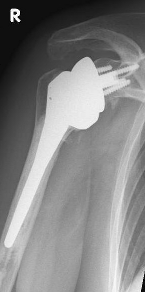

Abbildung6Conventional stem prostheses for omarthrosis and acetabular wear

left: X-ray image of a shaft prosthesis

right: anatomical shoulder prosthesis with glenoid replacement (Affinis type, Mathys company)